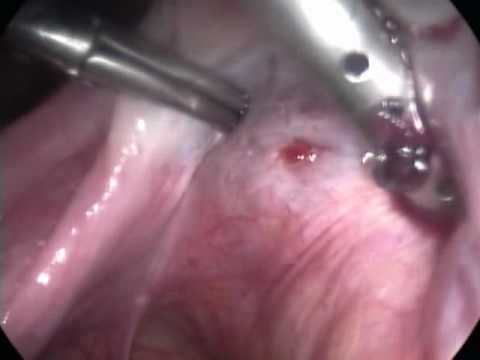

Histeroscopia: diagnostico e tratamento: polipectomia

Laparoscopia (P.O.)